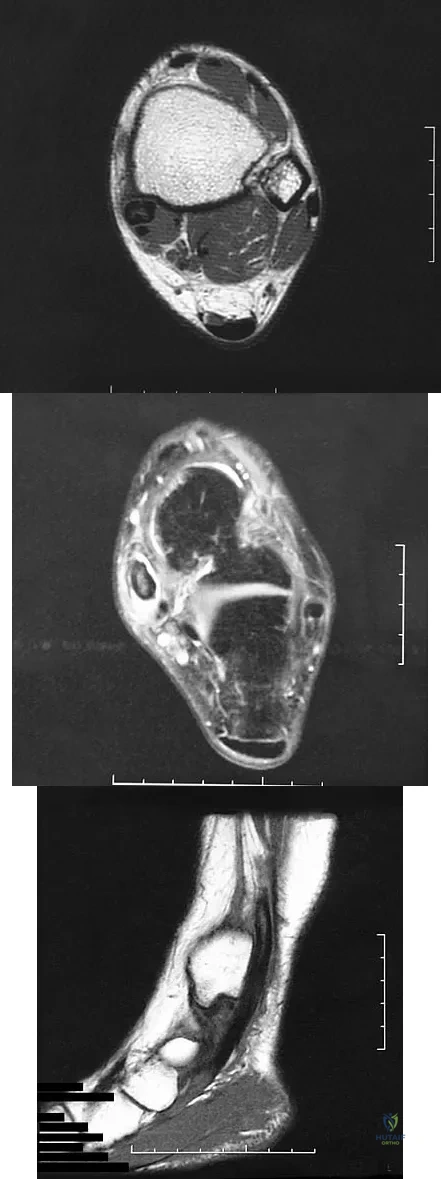

A 58-year-old man with type 1 diabetes mellitus is seen in the emergency department and he reports a 3-day history of a red swollen foot but no history of trauma. Examination reveals that the skin is intact, and the patient has discomfort with passive range of motion at the ankle, hindfoot, and midfoot joints. He denies any fever. Laboratory studies show a WBC count of 7,800/mm3, an erythrocyte sedimentation rate of 40 mm/h, a C-reactive protein level of 23, and a serum glucose of 100. A radiograph and MRI scans are shown in Figures 16a through 16c. What is the next most appropriate step in management?

Explanation